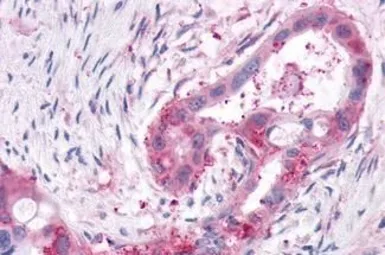

XPR1 antibody

Cat. No. GTX13290

ApplicationsICC/IF IHC-P